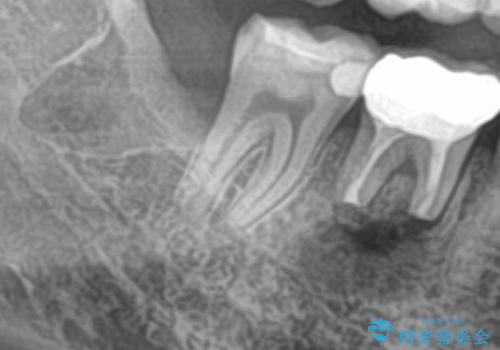

- 右下の親知らずを抜きたいとのことで来院された患者様です。

CTで神経の位置などを確認し、抜歯術を行いました。